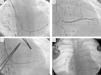

Foi obtido um acesso vascular através da veia subclávia direita, com implantação de elétrodo no ventrículo pulmonar, de fixação passiva – Fineline II Sterox 4457 (Boston Scientific) – e implantação de elétrodo auricular, de fixação ativa – Fineline II EZ Sterox 4457 (Boston Scientific) – na parede livre da AD. O SC foi cateterizado com bainha e auxílio de cateter diagnóstico de eletrofisiologia (Figura 4A). Foi obtida uma venografia do SC (Figura 4B), de modo a avaliar a veia tributária mais adequada para a entrega do eletrocateter de estimulação do ventrículo sistémico. Um eletrocateter bipolar (Boston Scientific) foi introduzido em veia póstero‐lateral, através de um fio guia (Figura 4C), com um bom limiar de estimulação e sem estimulação diafragmática. Os três elétrodos foram conectados ao sistema de pacing biventricular – Boston Scientific INVIVE (Figura 4D) – tendo o procedimento decorrido sem complicações. Com pacing biventricular a duração do QRS diminuiu de 196ms para 144ms (Figura 4B).

Implantação de sistema de ressincronização cardíaca por via subclávia direita, em paciente portadora de sistema de pacing DDDR à esquerda. A – Cateterização do seio coronário com o cateter diagnóstico e posterior introdução de cateter guia sobre o cateter. B – Venografia do seio coronário, revelando duas veias tributárias passíveis para entrega de eletrocateter de estimulação do ventrículo sistémico. C – Introdução de fio guia, através do cateter, na veia póstero‐lateral e posterior introdução de elétrodo de estimulação do ventrículo sistémico. D – Resultado final após a implantação de CRT, com elétrodos na aurícula direita, ventrículo pulmonar e ventrículo sistémico.